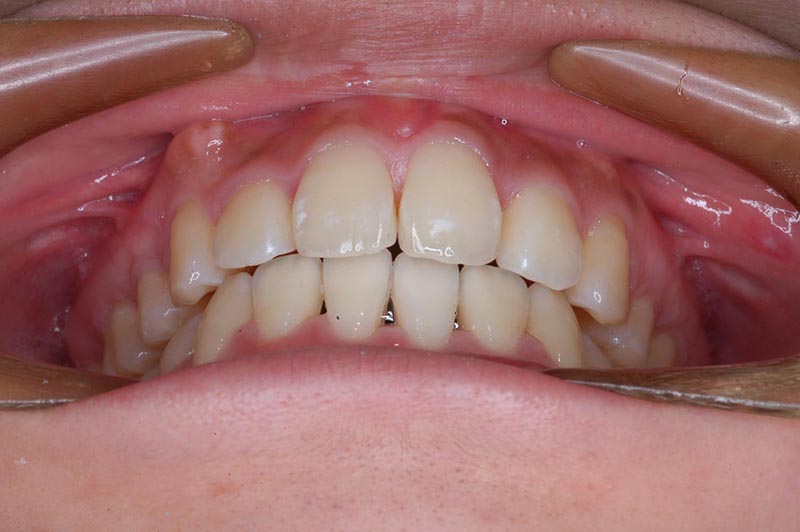

初診時

主訴 口が閉じづらい 診断名 アングルⅠ級上下顎前突症例

初診時年齢 19歳5ヵ月 性別 動的治療期間 26ヵ月

口腔内所見 大臼歯関係はⅠ級。顔面正中に対して上顎正中は一致しており、下顎正中は右側に偏位していた。上下顎前歯は大きく唇側傾斜し、overjetが7.8mmの上突咬合、両突歯列、叢生歯列弓であった。